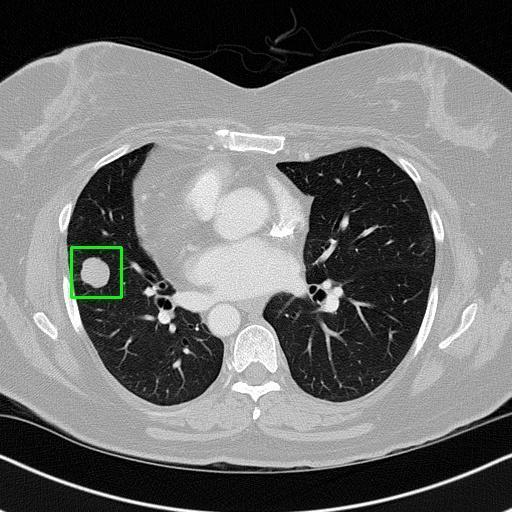

We developed an AI-based system using deep learning models for analyzing lung CT scans to detect and classify pulmonary nodules. We chose the YOLOv11 architecture for its enhanced object detection capability and adapted it specifically for medical imaging, incorporating pixel-level precision and severity classification.

Classification into three severity levels with colored bounding boxes.

Successfully built and deployed an AI model (YOLOv11) capable of detecting lung nodules in CT scans with high accuracy and real-time performance.

Achieved ~0.90 mAP@0.5 on validation data, showing strong object detection capabilities even on complex medical images.

Designed a severity classification system that categorizes nodules into null, moderate, and severe using colored bounding boxes, assisting in rapid clinical decision-making.